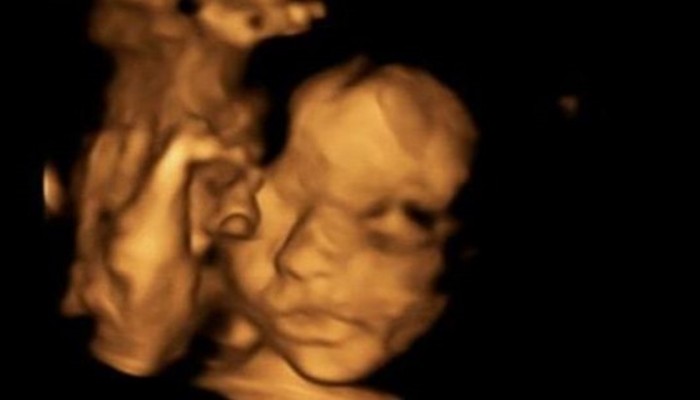

أجرى أطباء في بريطانيا عملية جراحية غير مسبوقة لجنين في بطن أمه في أسبوعه الرابع والعشرين، قبل إعادته إلى الرحم.

وأخرج الأطباء الجنين الأنثى من رحم الأم، حيث قاموا بإجراء عملية دقيقة استمرت أربع ساعات لإصلاح مشكلة في المنطقة السفلية من الحبل الشوكي (الصلب المشقوق - Spina bifida).

وكانت الأم بيثام سمبسون أمام خيار إسقاط الحمل في أسبوعه العشرين، لكنها اختارت اللجوء لهذه العملية المعقدة لتقليل احتمال تطور المشكلة لدى الجنين. وتتضمن العملية التي أجراها أطباء بريطانيون من جامعة كينغز كوليدج وأطباء بلجيكيون في مستشفى "أولد غريت أرموند ستريت" المتخصص بالأطفال في لندن، في كانون الثاني/ يناير، فتح بطن الأم في عملية تشبه العملية القيصرية، ثم إخراج الجنين من الرحم دون قطع الحبل السري، لتتم معالجة الشق الذي يكون مكشوفا للأطباء، وإعادة الجنين إلى مكانه لاستكمال فترة الحمل في بطن الأم. ويتوقع أن تضع الأم طفلتها إلويس في نيسان/ أبريل القادم.